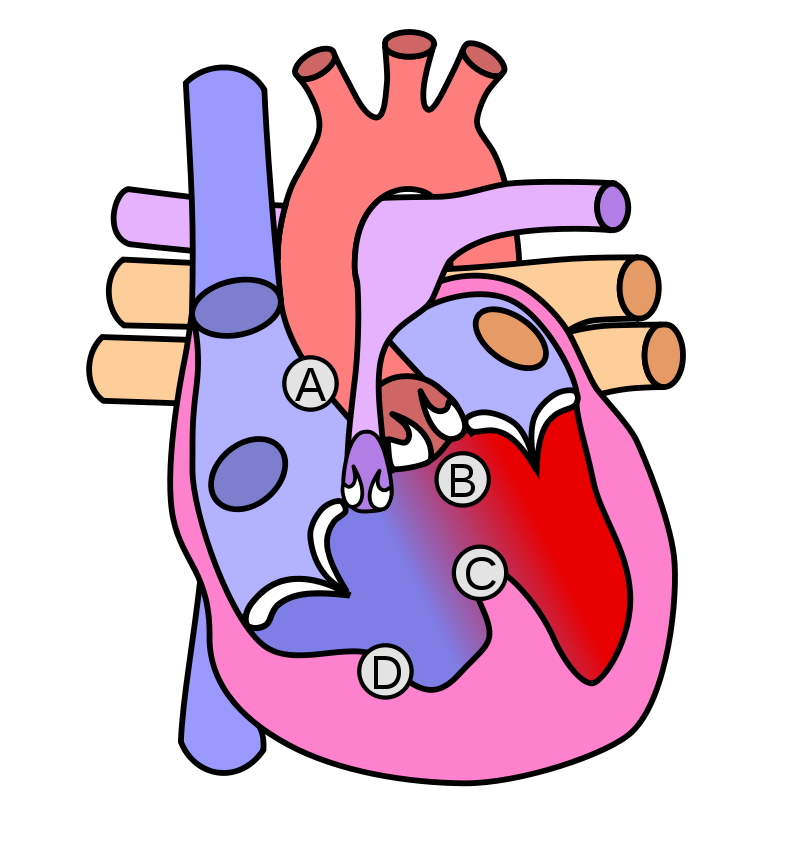

Tetralogy of Fallot (ToF)

Tetralogy of Fallot (ToF) is a congenital cardiovascular anomaly that includes:

- Right ventricular outflow tract stenosis

- Right ventricular hypertrophy

- Ventricular septal defect (VSD)

- An overriding aorta

Early cyanosis is caused by right-to-left shunting, and the degree of stenosis dictates how much shunting and cyanosis is present.

In response to a cyanotic spell, patients with tetralogy of Fallot (ToF) are taught to squat because:

- Artery resistance is increased.

- Reduces shunting and increases blood flow to the lungs

Tetralogy of Fallot (ToF) radiology of the heart shows a “boot-shaped” heart.